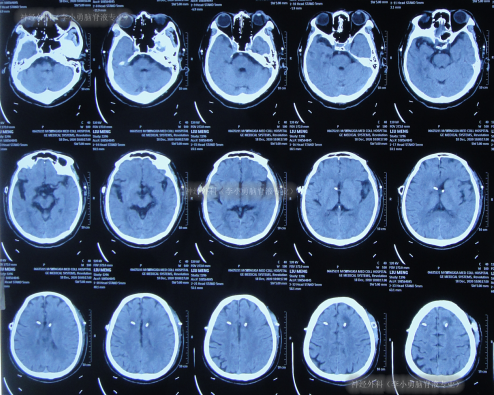

左侧脑室腹腔分流术后继续治疗10天,期间2次查头颅CT(图-9),虽意识基本正常,但记忆力差,吞咽动作慢,偶呛咳,小便失禁。

图-9:2次查头颅CT

左侧脑室腹腔分流术后即2020年12月28日出院,出院时仍记忆力差,吞咽动作慢,偶呛咳,例行检查头颅CT(图-10)后出院。

图-10:2020年12月28日头颅CT